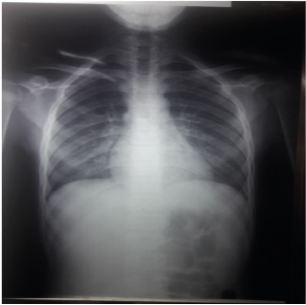

A chest X-ray revealed diffuse bilateral interstitial prominence (figure 1). Chest computed tomography realized after 5 days was normal.

Figure 1.  Chest X-ray, Diffuse Bilateral Interstitial Prominence

Chest X-ray may be normal in 22% cases. CT chest findings include ground glass opacities, alveolar infiltrates, and consolidations. Radiologic resolution may be seen after 3 and 4 days if the hemorrhage ceases [7].